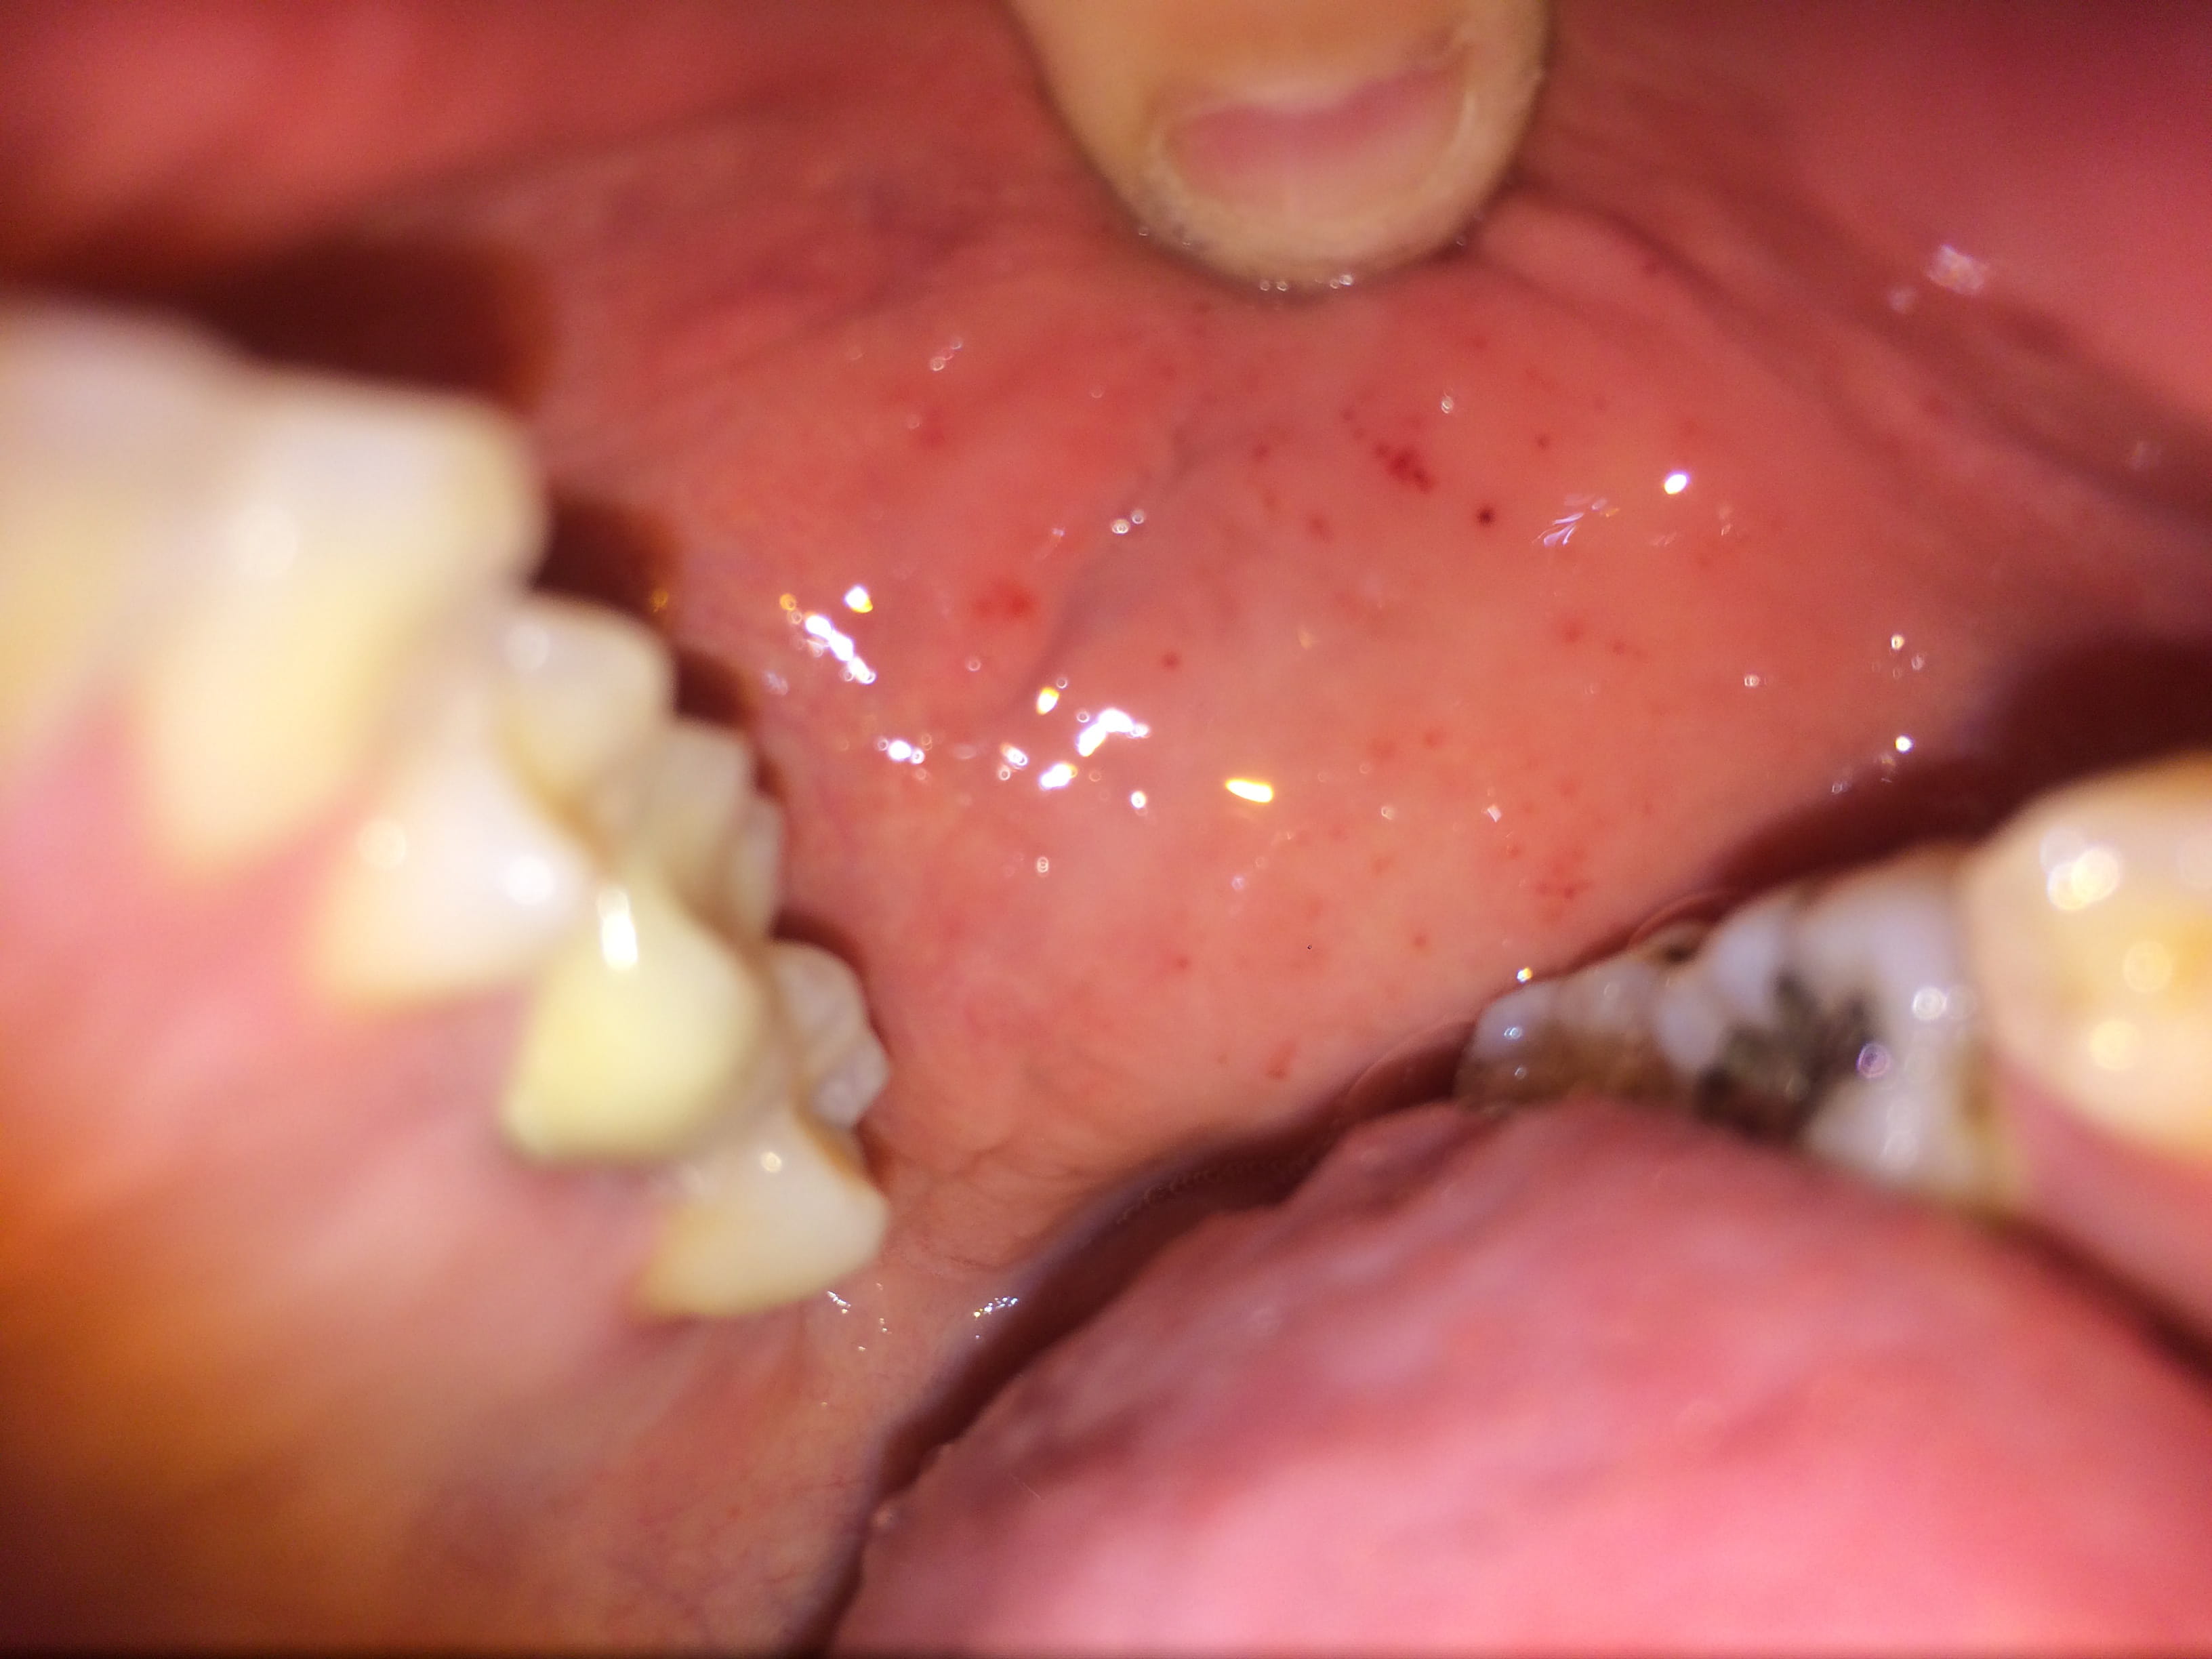

Voila depuis quelques jours j'ai des petits points rouges à l'intérieur des joues et sur le bord de la lèvre intérieure.

Ils s'estompent et reviennent.

Quelqu'un a t-il deja eu Ca?